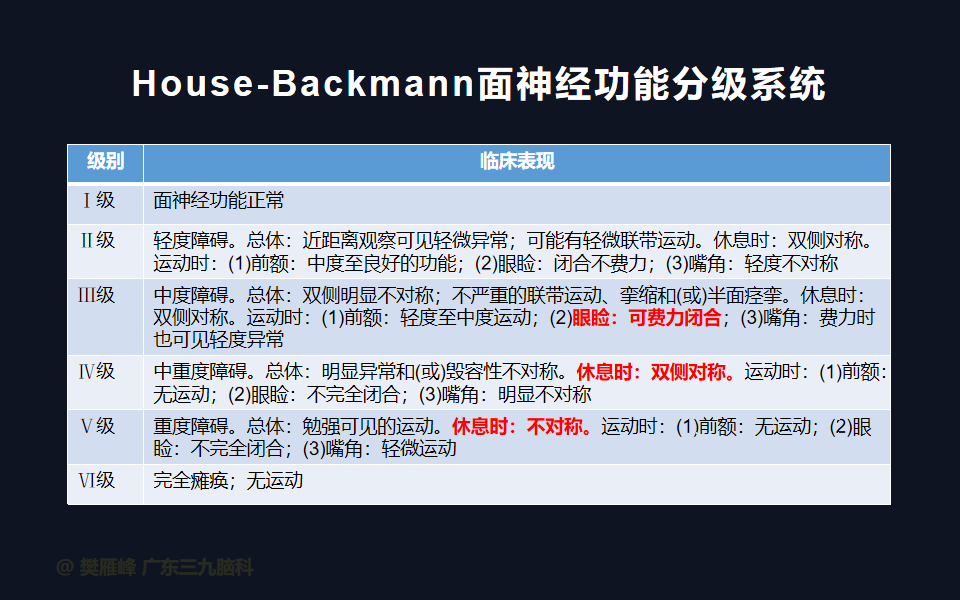

面神经功能障碍是显微手术切除的主要神经系统并发症。经迷路和乙状窦后入路的次全切除和近全切除相对于全切除显示了更好的术后面神经结果。完全切除肿瘤是和面听神经保存之间的妥协,是所有神经外科医生和所有患者在治疗前都应做好充分的准备。

在这个二维手术视频中,展示了一种经枕下乙状窦后入路束膜下分离保留面神经的方法。患者是一名51岁的男性,有1年右耳听力下降伴耳鸣、无步态不平衡病史,术前有右侧轻度面瘫,神经影像学显示右侧桥小脑角区约30×30×29mm的囊实性占位,增强后实性部分及囊壁可见明显强化。他接受了经乙状窦后入路保留面神经的方法,术中肿瘤全切除,面神经被肿瘤挤压成薄膜状覆盖于三叉神经表面。术后面瘫加重,听力未能保留,神经影像学显示肿瘤全部切除。我们展示了安全的颅神经保护和肿瘤切除的细微差别和技术要点,以及手术技术。